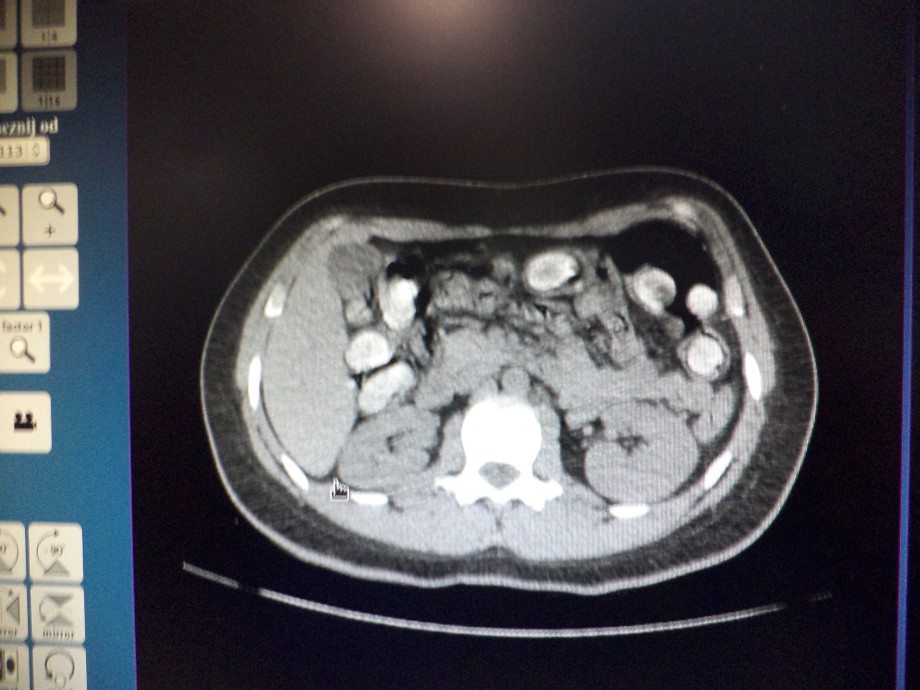

Podróżna została skierowana przez funkcjonariuszy Wydziału Zwalczania Przestępczości Izby Celnej w Warszawie do kontroli celnej z przejścia „nic do zgłoszenia” (tzw. zielonej linii). Zważywszy na czas trwania podróży i przede wszystkim jej kierunek, podróżna została poddana wstępnym testom na obecność narkotyków w ślinie, następnie w moczu. Mimo niejednoznacznego wyniku narkotestów, podjęto decyzję o przewiezieniu podróżnej do szpitala, celem przeprowadzenia badania lekarskiego na obecność narkotyków w organizmie. Wykonane w szpitalu badanie tomografii komputerowej przewodu pokarmowego, potwierdziło podejrzenia funkcjonariuszy celnych, że narkotyki przemycane są wewnątrz organizmu. Podróżna zatrzymana została w szpitalu, celem wydalenia kapsułek z narkotykiem.

Przemycana w żołądku kokaina zapakowana była w 80 kapsułek o łącznej wadze 0,75 kg. Wewnątrz każdej znajdowało się około 9 g narkotyku.